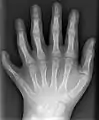

У людей и животных она может проявляться как на одной, так и на обеих руках. Обычно дополнительный палец представляет собой небольшой кусочек мягкой ткани, которую можно удалить. Иногда это просто кость без суставов; очень редко лишний палец бывает полноценным. Дополнительный палец чаще всего образуется со стороны мизинца, реже на стороне большого пальца и очень редко между средними пальцами. Обычно лишний палец является аномальным разветвлением обычного пальца, редко возникает на запястье, как обычный палец.

![]() |

![]() | |

postaxial |

preaxial |